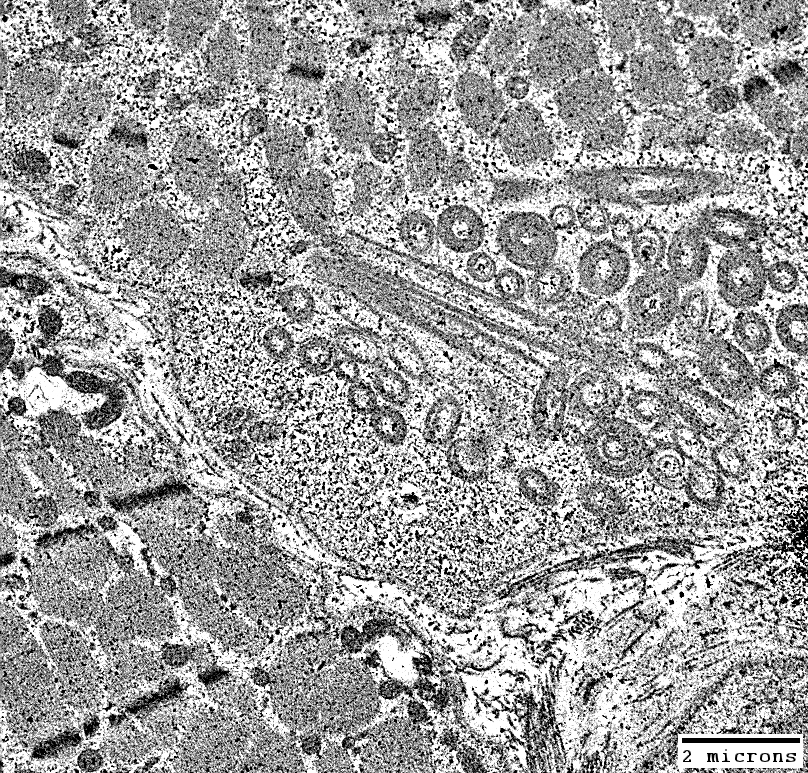

Membrane Aggregates in Muscle Fibers

From C Cai